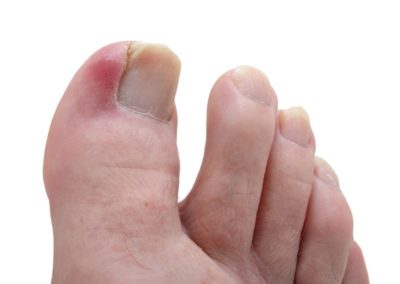

Каталог заболеваний Часто запрашиваемые в Мариуполе Аллергия Ангина Аппендицит Бронхит Варикоз Ветрянка (Ветряная оспа) Гастрит Геморрой Герпес Молочница (Кандидоз) ОРЗ Остеохондроз Панкреатит Пневмония Простатит Псориаз Сахарный диабет Стоматит Тонзиллит Туберкулез АБВГДЖЗИКЛМНОПРСТУФХЦЧШЭЮЯ Болезни на букву В Вагинит Варикоз Варикоцеле Васкулит Вегетососудистая дистония Везикулит Ветрянка (Ветряная оспа) Вирус иммунодефицита человека, СПИД Вирусные бородавки Вирусный энцефалит Внематочная беременность Внутримозговое кровоизлияние Внутриутробная гипоксия Водяница (Дисгидроз) Воспаление седалищного нерва (Ишиас) Воспаление слуховой (евстахиевой) трубы Вросший ноготь Вульвит Вульвовагинит Вывих сустава Вывих челюсти Выпадение матки и влагалища Выпадение прямой кишки